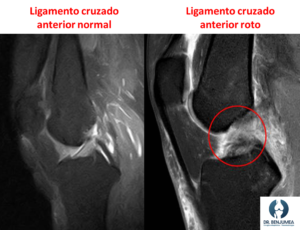

¿Cómo se diagnostica la rotura del ligamento cruzado anterior?

Fundamentalmente el traumatólogo se basa en los síntomas y en la exploración física del paciente. Existen una serie de maniobras específicas que nos ayudan a saber si los pacientes padecen esta rotura con bastante fiabilidad.

El diagnostico siempre deberá ser confirmado por resonancia magnética, que nos dará una visión de toda la rodilla y podremos ver si existen otros tipos de lesiones asociadas en los meniscos, cartílago o ligamentos.